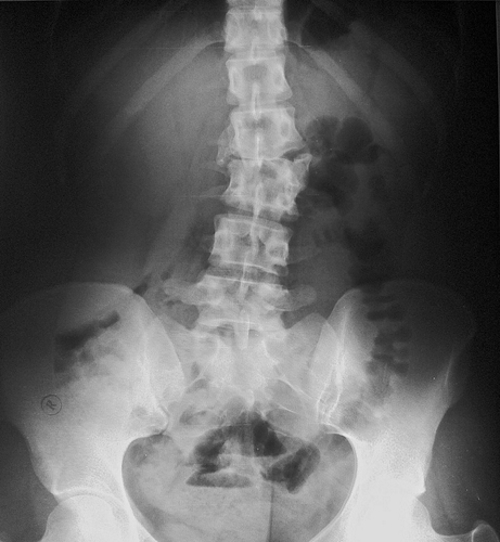

Для исследования поясницы предпочтителен функциональный рентген. Снимки выполняются в боковой проекции, когда пациент находится в лежачем положении с максимальным разгибанием. Более информативной будет рентгенография спины в положении сидя или стоя. Однако технические возможности рентгеновского кабинета не всегда позволяют использовать этот метод.

Чтобы получить полное представление, снимки делают в трех проекциях. Первый снимок выполняется сзади. Второй — сбоку при максимальном сгибании спины. Третий также сбоку, но при максимальном разгибании тела.

При рентгенографии поясничного отдела врач анализирует структуру костной ткани позвонков, оценивает наличие жидкости и выявляет деформации межпозвоночных дисков. Специалист ставит диагнозы, связанные с заболеваниями позвоночника.

Рентгенологическое обследование может выявить следующие патологии: